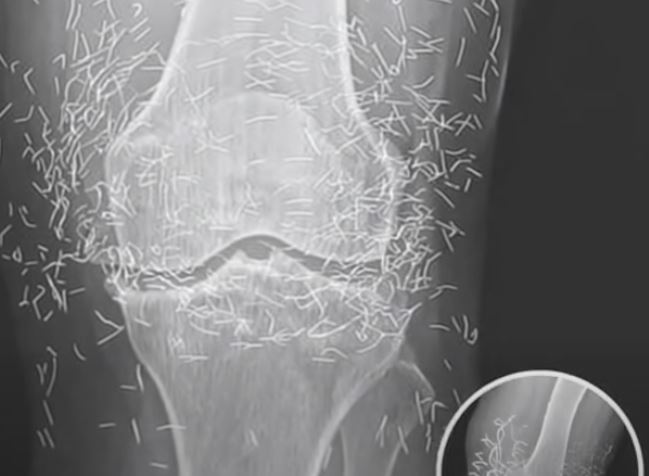

What started as a routine hospital visit for knee pain turned into a medical mystery that left doctors speechless. A 65-year-old woman in South Korea went in expecting a diagnosis of arthritis — but when her X-ray appeared on the screen, the room fell silent. Her knee joint wasn’t just worn down from age; it was filled with dozens of tiny gold needles. The strange discovery sparked immediate questions about how they got there and why they had remained unnoticed for so long.

Doctors soon learned that the woman had been struggling with osteoarthritis for years, a condition that makes everyday movement painful as cartilage breaks down. Frustrated by the limits of conventional medicine, she had turned to acupuncture — a centuries-old therapy believed to ease pain and improve circulation. But instead of using temporary needles, her acupuncturist had inserted fine gold ones beneath the skin permanently, convinced they would provide lasting healing energy.

The shocking X-ray served as a cautionary reminder of how alternative treatments can sometimes go too far. Specialists warn that leaving any metal object inside the body can cause inflammation, infection, and complications during imaging procedures. While acupuncture, when performed properly, is generally considered safe, experts emphasize that permanent implants are not medically approved or supported by evidence.